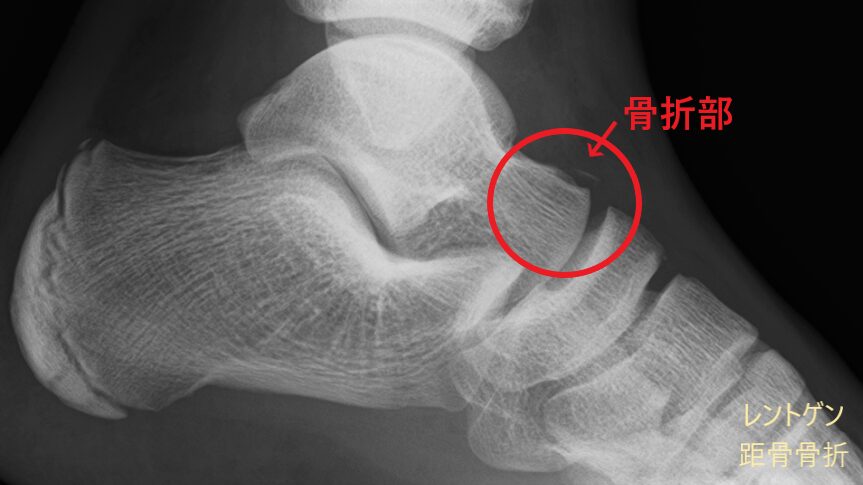

レントゲン画像には映りにくい筋肉や腱、靭帯などの状態に加え、骨の様子もあわせて確認できます。